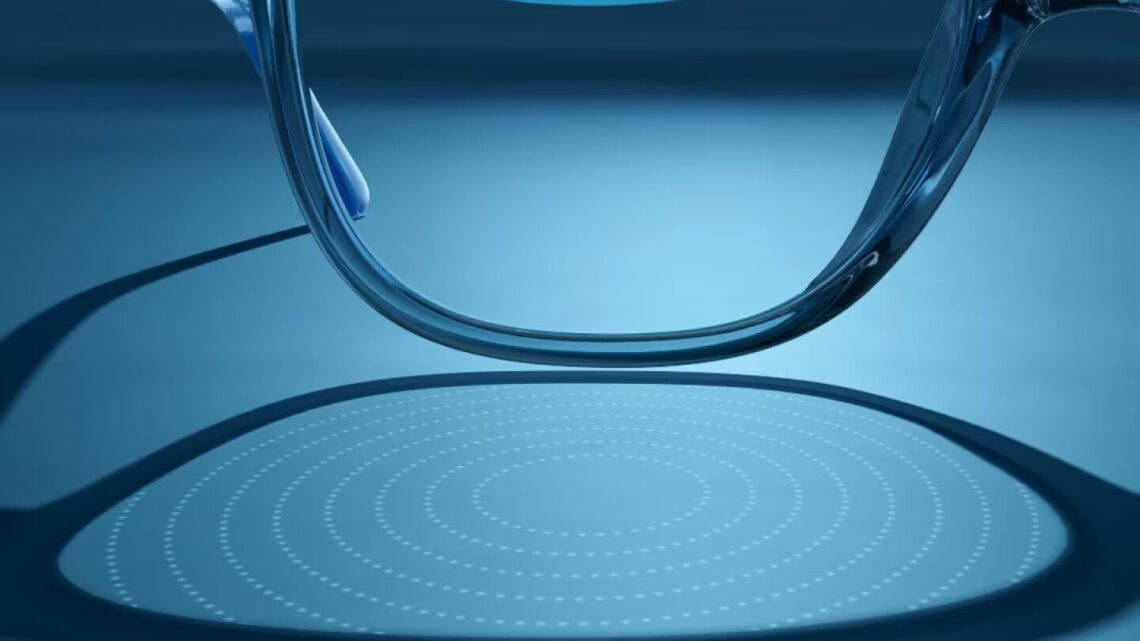

De glazen bevatten 11 concentrische ringen met kleine verheven stippen, die het licht refractioneren zodat het beter op het netvlies wordt gericht, in de hoop de lengtegroei van het oog te vertragen. Volgens Repka telt de wetenschap slechts gedeeltelijk of deze hypothese uiteindelijk bevestigd zal worden, maar de glazen lijken effectief te zijn, ongeacht de onderliggende wetenschap.